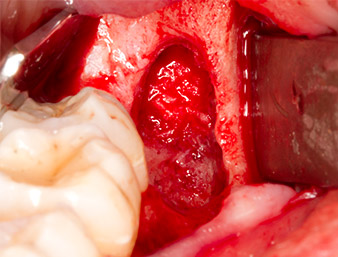

El tejido situado por encima del resto radicular no se había osificado por completo y constaba en su mayor parte de un tejido granulado con alteraciones inflamatorias (figura 4).

El tejido inflamatorio periapical se retiró también con sumo cuidado utilizando un excavador manual. La figura 12 muestra el alvéolo vacío con el nervio alveolar inferior expuesto.